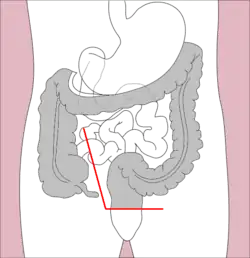

Sigmoidectomy is a resection of the last part of the colon, known as the sigmoid colon, and can include part or all of the rectum (proctosigmoidectomy). Precancerous polyps and sigmoid colon cancer are common indications for sigmoidectomy. Benign indications for sigmoidectomy include diverticular disease, especially when complicated by perforation or fistulae, sigmoid volvulus, trauma, and ischemic or infectious colitis.[11] When a sigmoidectomy is followed by terminal colostomy and closure of the rectal stump; it is called a Hartmann operation. This is usually done out of the impossibility of performing a "double-barrel" or Mikulicz colostomy, which is preferred because it makes "takedown" (reoperation to restore intestinal continuity using an anastomosis) considerably easier.[23]